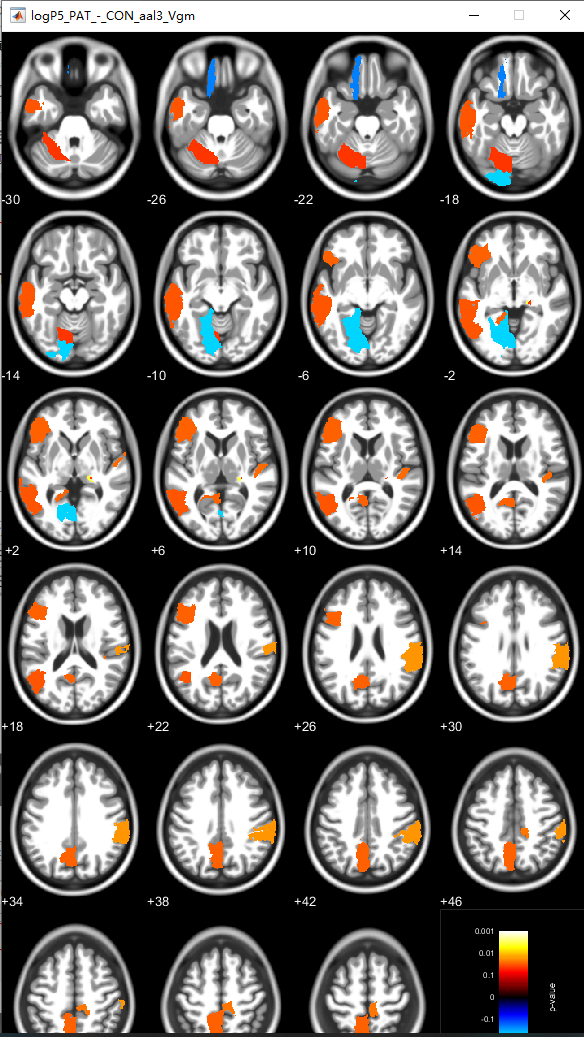

便有了下面的两张图片,第一张其命名原则是:logPThreshold_Nameofcontrast_NameofAtlas_measure.nii。

所以此处的结果表示小编取得p值是0.05,contrast的命名为PAT-CON,采用的atlas图谱为aal3,寻找的是灰质体积在aal3图谱上的差异。此处有一些疑问,就是小编到底计算的是做的是vertex水平还是ROI水平?不知道读者中有没有明白的,小编想了好久,不是特别敢确定。但是小编猜想是ROI的,请继续往下看小编的一个证据。

在这里插入图片描述

证据在此: 下图是用xjview工具包查看的结果图,注意看文件名,在玻璃脑中显示的是一块一块的,ROI便是区域性的,